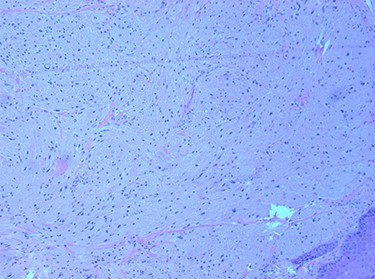

Histopathological examination revealed large cells with granular eosinophilic cytoplasm and nuclei with scattered mild to moderate atypia. These cells expressed CD68, CD56 and S100, and lacked expression of AE1 and AE3. Focal spindling of cells was present with no obvious necrosis or mitosis. The squamous surface epithelium was orthokeratizing with mild pseudoepitheliomatous hyperplasia (Figs 5 and 6).

tumour cells with abundant granular cytoplasm and sub-epithelial proliferation. H & E 100×.

GCT can be identified by histopathological studies using haematoxylin and eosin (H&E) staining, which shows polygonal, large cells clustered in nests or sheets with coarsely granular eosinophilic cytoplasm [5, 7–9]. Malignant GCTs are characterized by histologic features such as tumour necrosis, increased mitotic index and spindling of cells, but clinical behaviour such as metastasis must also be taken into account [9]. Immunohistochemical staining of GCT has been shown in the literature to be positive for S-100 protein [1, 3–10], PAS [7, 9, 10], neuron-specific enolase [3–7, 9], vimentin [5, 7] and CD68 [6, 7, 9, 10]. In our case, S-100 and CD68 were positive with PAS. The presence of pseudoepitheliomatous hyperplasia (reactive epithelial proliferation with pseudoinfiltrative growth pattern) is common in GCT and can be confounding in some instances, as it may be mistaken for well-differentiated SCC especially if small biopsies are taken [3].